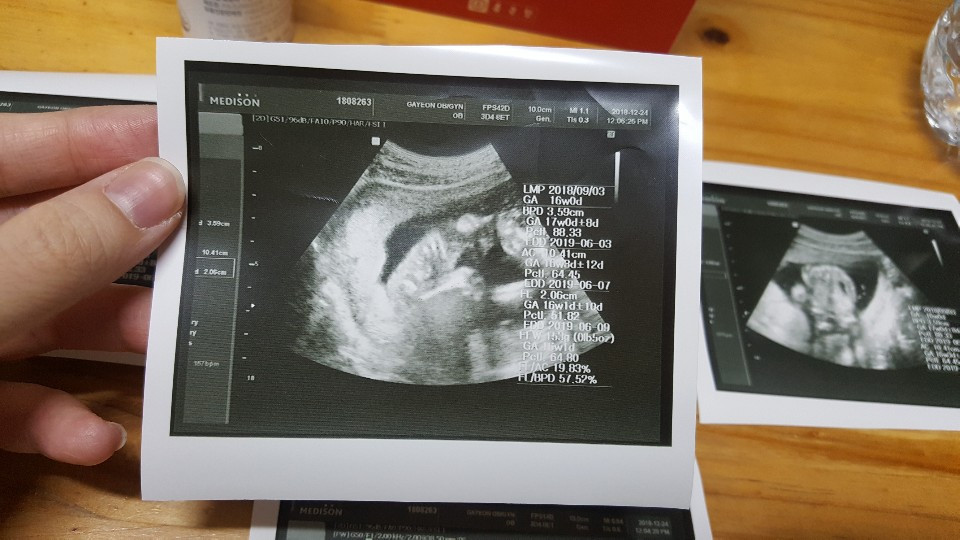

몸이 너무 힘들어 이틀을 고생하고 간 병원에서 본 꼬톨이의 초음파 모습은 역시나 너무나 감동이었다.

4주전 내가 알던 모습에서 정말 쑤욱 자라있었고, 척추도 선명하게 보여지고

이제 성별도 알 수 있는 시기가 되었네 :)

사실 선생님께 설명들으면서 볼때는 이해가 쏙쏙 되는데 초음파 사진을 받아서

가만히 보고 있으면 아직도 뭐가뭔지 잘모르겠다 :)

여기가 머리인가.. 발인가?

여튼 초음파 찍는동안 계속 팔다리 움직여주고, 움츠렸다 폈다가 어찌나 활발한지

의사선생님께서 머리크기도 평균이고 몸무게도 주수대로 잘 자라고 있다니 지금 내가 아픈게 크게 대수롭지 않게 여겨진다. 이게 엄마의 마음인가?